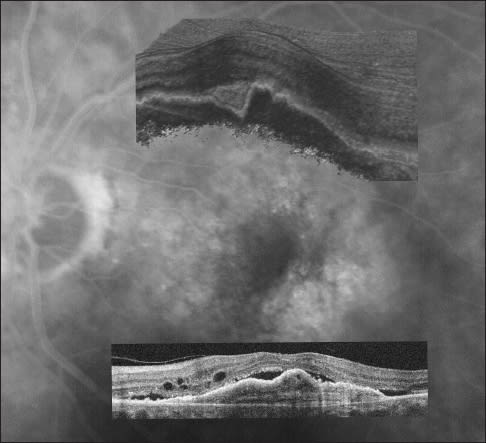

A fluorescein angiogram of a four disc-area occult choroidal neovascular membrane in a patient with neovascular age-related macular degeneration, with superimposed corresponding spectral-domain optical coherence tomography image (inferior) and macular cube section (superior). The OCT images demonstrate choroidal neovascularization, retinal pigment epithelial detachment, subretinal fluid (serous retinal detachment) and macular edema with associated disruption of the foveal photoreceptor layer and external limiting membrane.